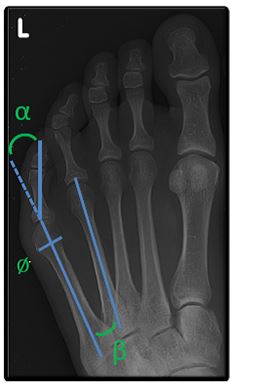

Die bunionette ontstaat meestal door een lichte scheefstand van het vijfde middenvoetsbeentje en overdruk van te smal schoeisel.

De belangrijkste behandeling bestaat uit goed schoeisel eventueel aangevuld met steunzolen. Bij ernstige pijnklachten of last kan een ingreep wenselijk zijn. Via een incisie van 2 à 3 mm brengen we een klein boortje in. We zagen hiermee een middenvoetsbeentje door, om de voet wat smaller te maken.